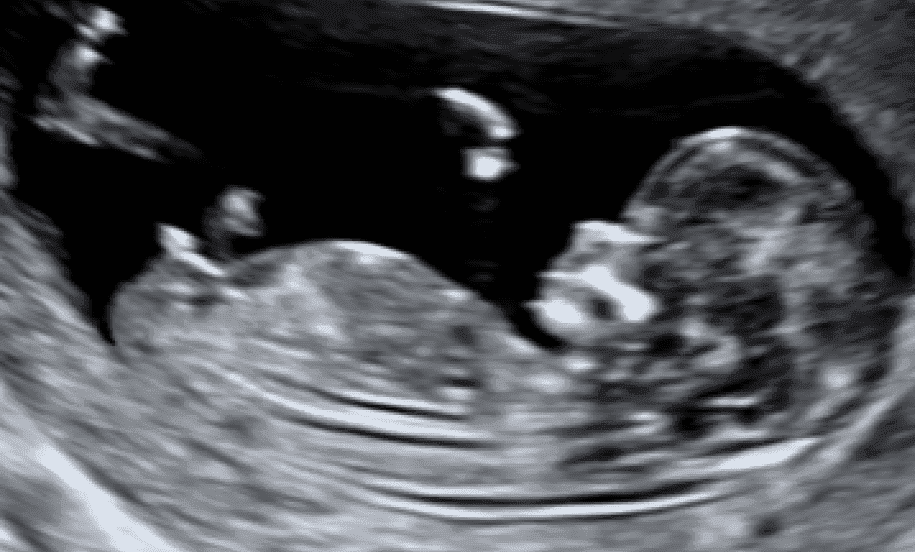

Dating Scan

- Confirm a single/multiple pregnancy of an early/viable pregnancy

- Determine fetal gestation age.

- Between 8 and 14 weeks.

- Crown Rump Length (CRL) measurement.

- Confirmation of heartbeat